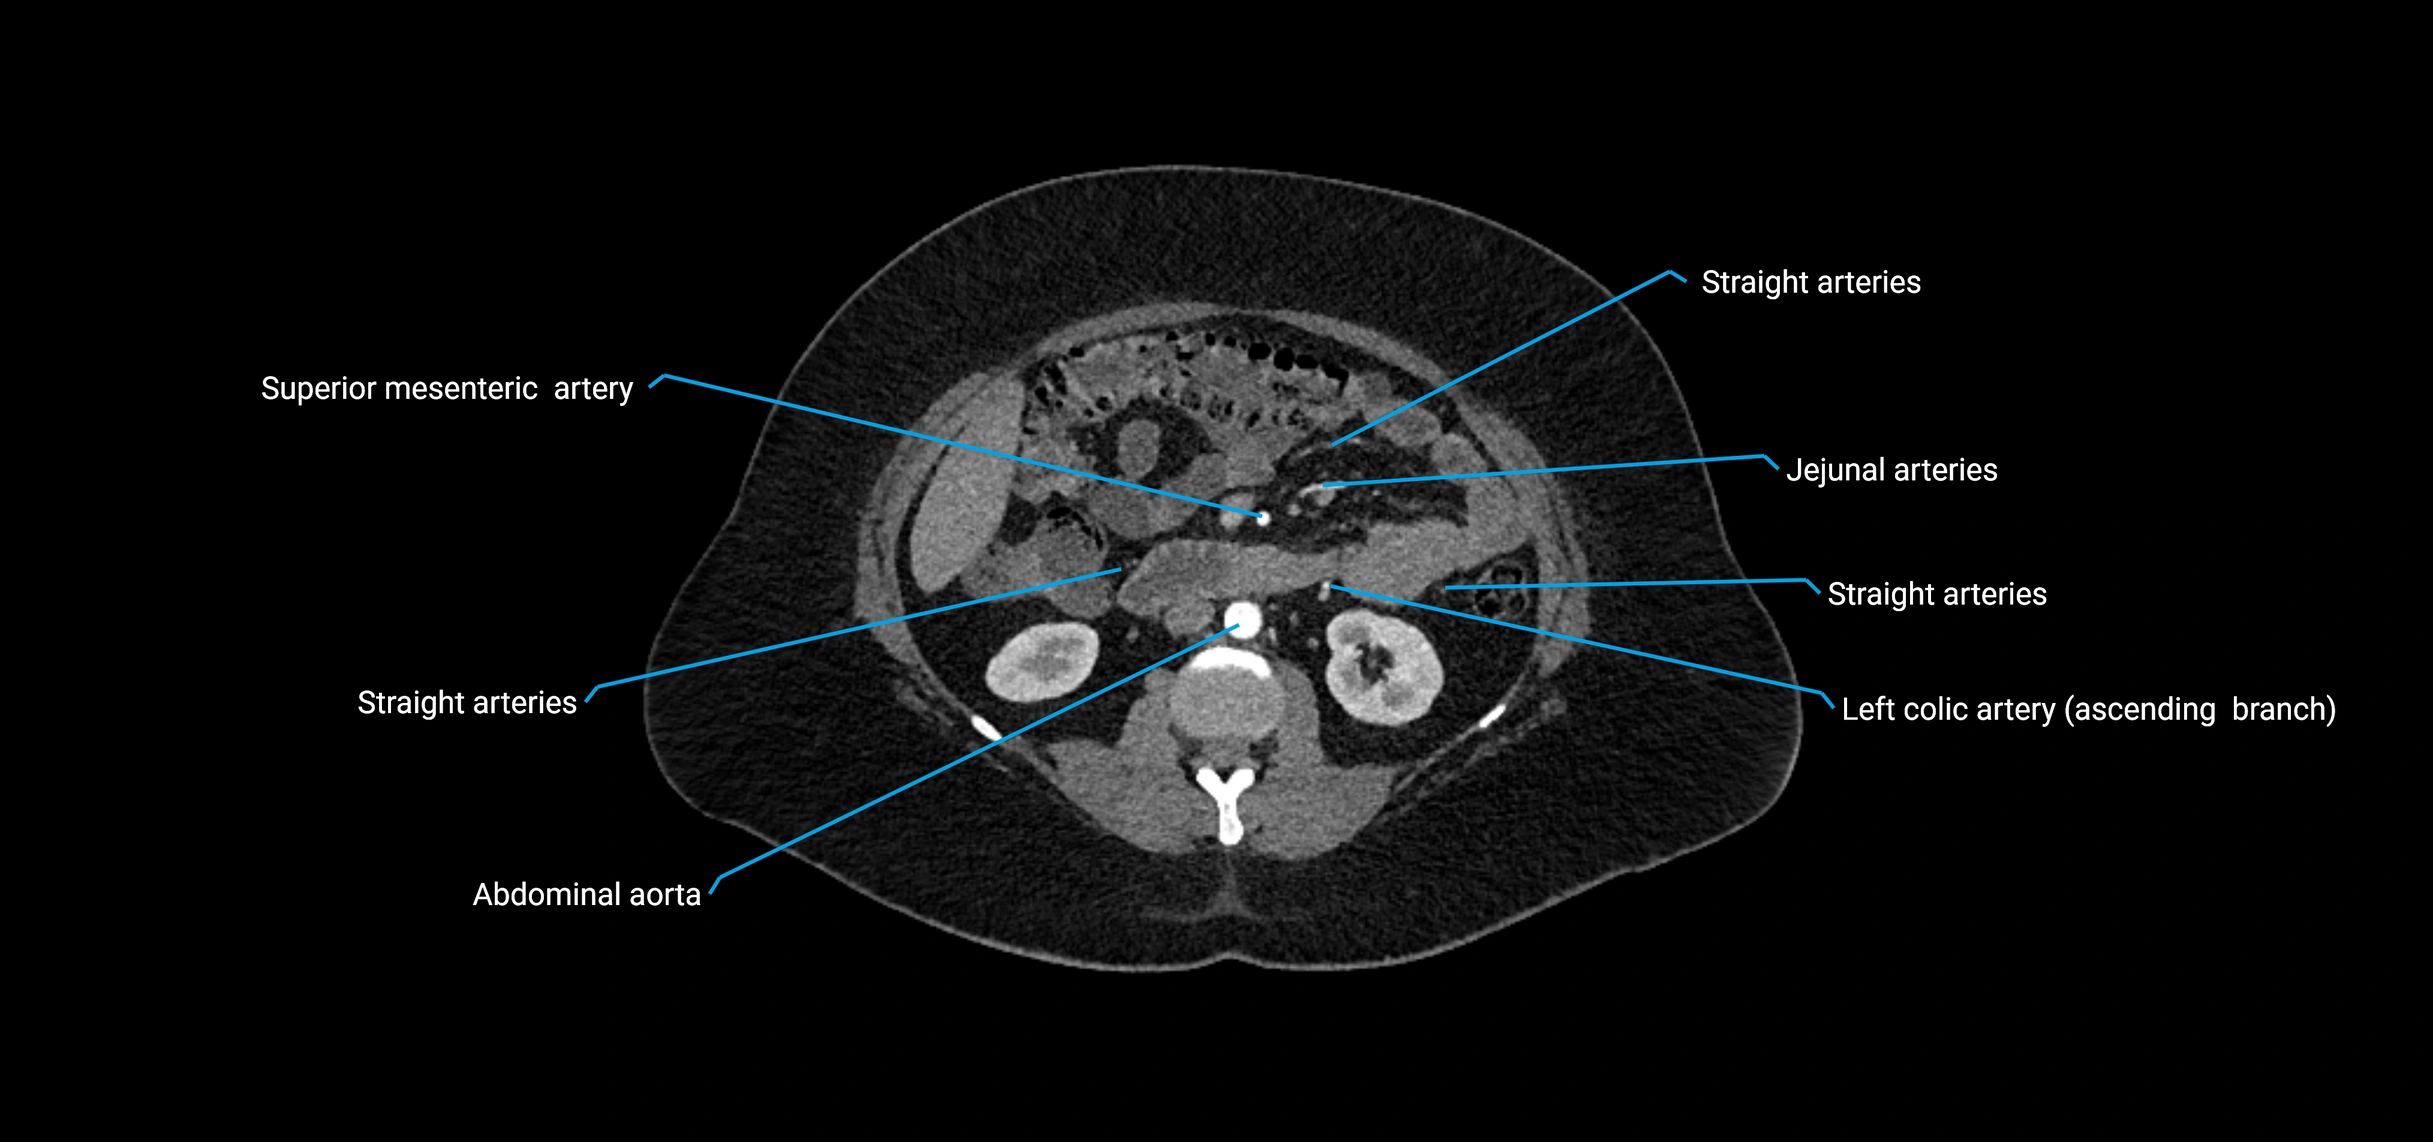

CT images

image

Contrast-enhanced CT (CTA):

• Gold standard for abdominal aortic imaging

• Provides excellent detail of lumen, wall, aneurysm, thrombus, and branch vessels

• Multiplanar and 3D reconstructions help in aneurysm measurement, stent graft planning, and dissection evaluation